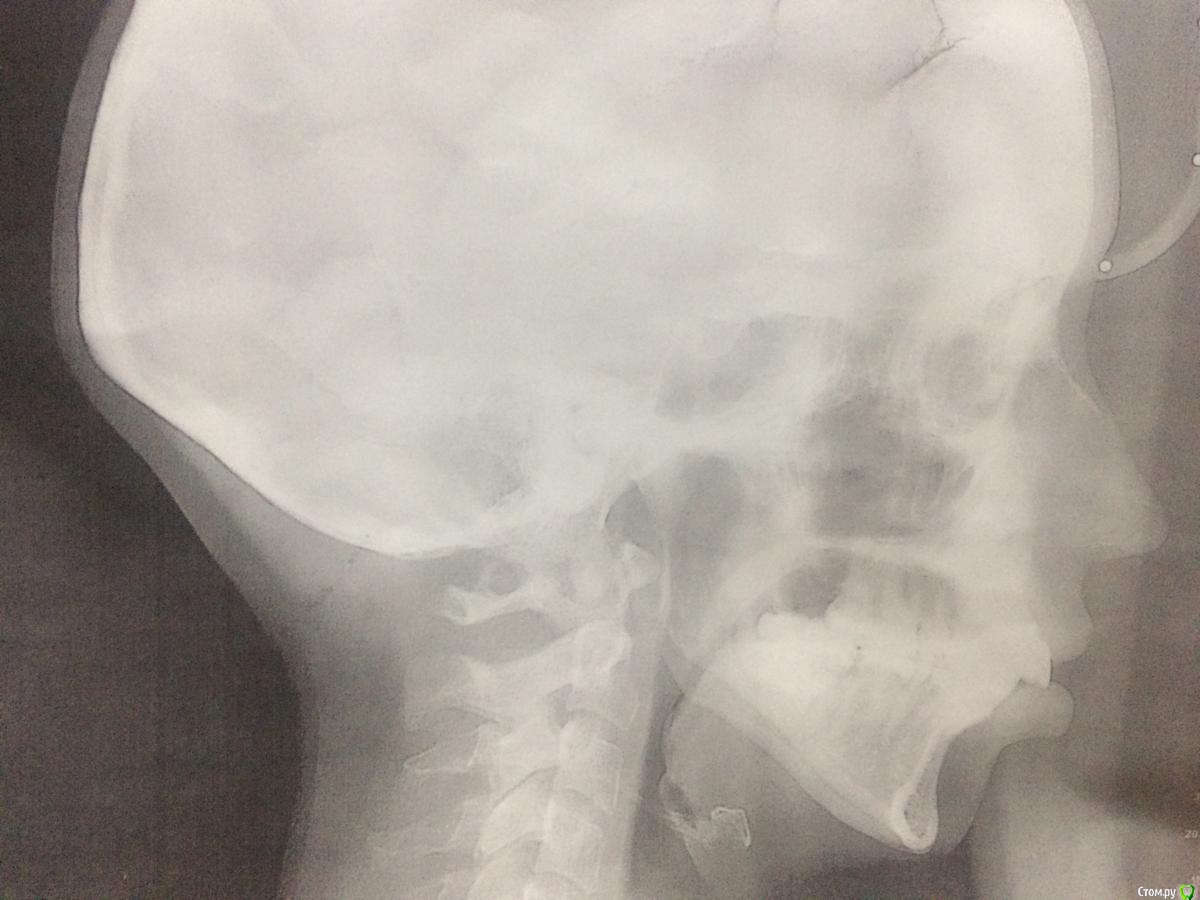

Здравствуйте, уважаемые специалисты! 10 лет назад сняла БС с верхней челюсти, удалены верхние 8-ки, нижние 8-ки пока в десне. Категорически хочу исправить ситуацию с несмыканием губ (смыкаются только напрягая подбородок), некрасивый профиль с торчащими под наклоном верхними зубами. Большинство врачей ортодонтов рекомендуют удаление верхних 4-к и засчет этого сократить щель и убрать наклон. На мои вопросы про возможные методы выдвижения вперёд нижней челюсти отвечают, что скорее всего она вернётся в старое положение так как мне уже 27 лет! Какой возможный выход вы видите в моей ситуации?

перемещение нижней челюсти и возраст - не взаимосвязаны. Но в Вашем случае она действительно не станет кпереди  - в силу своей формы и размера.

Если действительно хотите кардинально поменять профиль - рассмотрите вариант сочетания лечения с ортогнатией. Возможно только так Вы получите желанный результат?